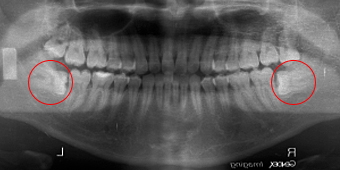

下顎両側水平埋伏智歯ですが埋伏の位置が上部なんですが 根っこが大きく開いている為少し難で15分ほどでした。